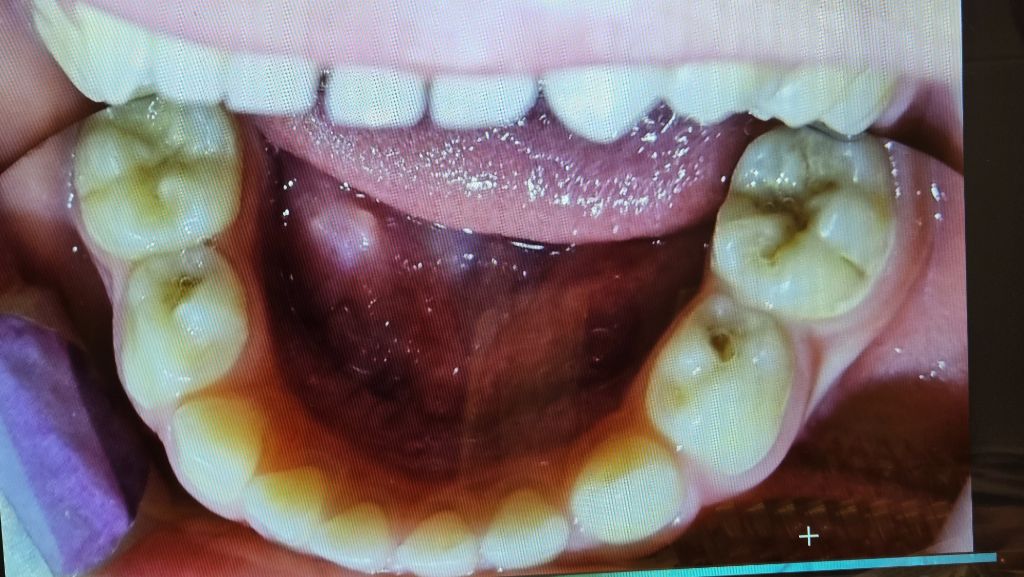

이 치과에서는 모든 어금니에 충치가 다 있으나 (보는 사람 기준) 왼쪽 위에는 매우 약해서 치료를 안 해도 될 수는 있다고 했습니다만 나머지 6개는 모두 치료가 필요하다고 했습니다.

타고난 체질과 현재까지 먹는 것에 대해서는, 2달 전에 웨스턴 프라이스 박사님의 전래식을 접하고 실천 중입니다. (어린이집에서 주는 건 어쩔 수 없고요) 다만 아이 성격인지 콩나물 콩 버섯 이런 걸 너무너무 좋아하고, 고기나 내장육은 잘 안 먹습니다... 전래식 알기 전에도 고기 먹여보려 했지만 잘 안 먹어서 그냥 좋아하는거 먹게 두었다가요, 전래식 알고 나서는 두달동안 엄청 노력해서 그래도 고기 좀 잘 먹게 되긴 했고요, 전래식 하는 지인 추천으로 선생님 치과랑 책도 알게 된 거에요. 하지만 2달 가지고 눈에 띄는 변화가 있진 않은 것 같아요. 늘 빈혈을 달고 살았는데, 요새 꽤 좋아지긴 했지만, 눈 밑에 다크서클이 항상 있고, 태어나길 장이 약한 편입니다. 제가 장이 약한데 그걸 물려받은 것 같아요.

아참, 아이가 신생아시절부터 항상 입을 약간 벌리고 자는데 (입술이 세모 모양이 됩니다) 이것도 턱의 구조와 관련이 있는지, 앞으로 고쳐주려면 어떻게 하면 좋을지도 궁금합니다!!

말씀하신 내용을 봐서는 아이도 턱이 작아서 구호흡을 하고 있을 가능성이 있습니다.

이런 점도 충치 발생에 큰 영향을 미칩니다.

초등 1학년 정도 쯤에 교정 상담을 받길 권합니다.